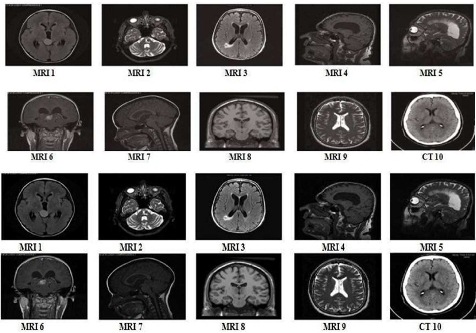

As mentioned earlier, different applications use Neuro- Wavelet based image compression techniques. Table 2 shows the results obtained using the neural network radial basis algorithm. Figure 7 shows the original medical images. Figure 8 shows the NNBP compression technique's resulted in compressed medical image. Figure 9 shows the comparison between the models with and without importance map (Li, et al., 2018). Those images give us some extra-ordinary idea about how different types of neural-network techniques are adopted for image compression, whereas the table contains a comparison of Compression Ratio, PSNR, Mean Square Error and BPP (Dabass, Vig, & Vashisth, 2018). It will give us some idea about different results obtained from different compression techniques using a combination of neural network Analysis and wavelet based decomposition.

Figure 7. Original Medical Images

Figure 8. NNBP Compression Technique's Resulted in Compressed Medical Image